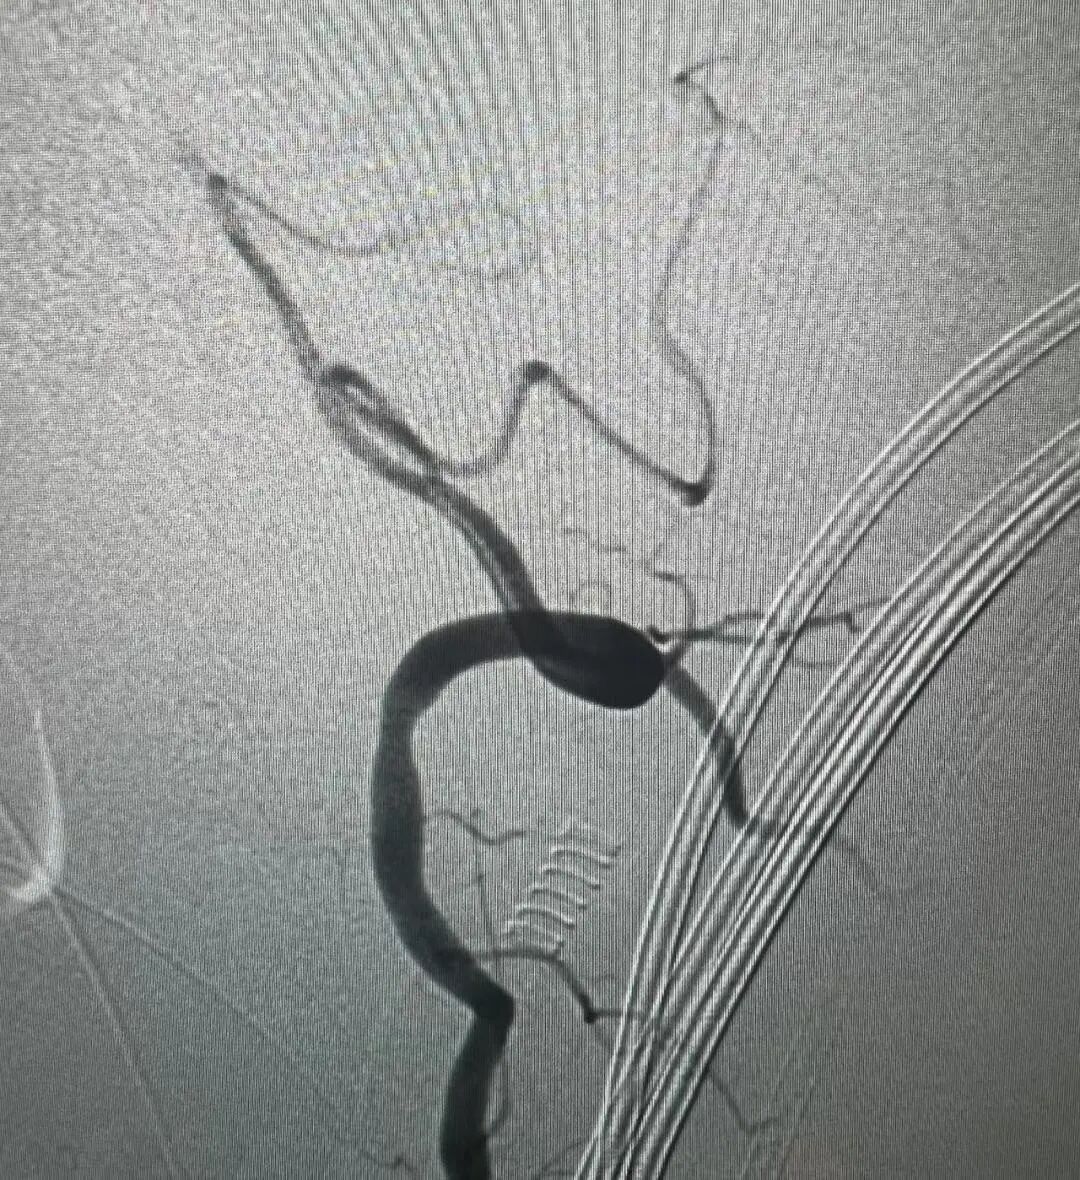

术前造影:左侧椎动脉V3段夹层,长度约37mm,基底动脉起始部以远未显影,双侧后交通开放,基底动脉未见造影剂充盈、返流。

左侧后循环

右侧后循环

左侧前循环

右侧前循环